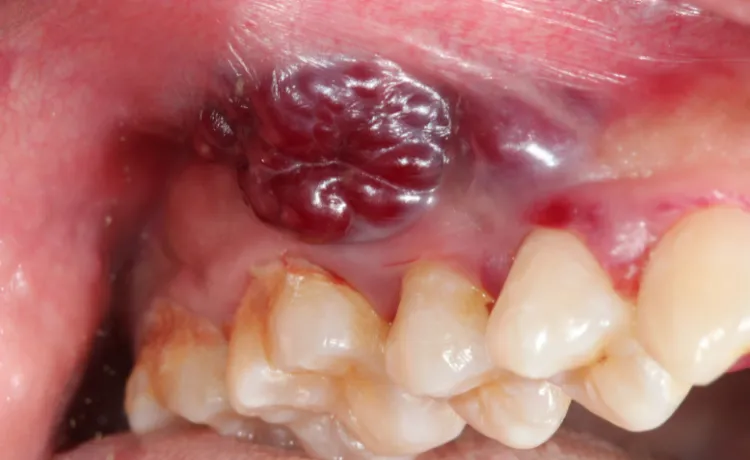

Rak jamy ustnej może objawiać się również jako guzek, zgrubienie lub obrzęk, który pojawia się w nietypowym miejscu na wardze, dziąśle, języku, a nawet wewnątrz policzka. Często te zmiany są wyczuwalne dotykiem, a co ważne, mogą być początkowo całkowicie bezbolesne. Właśnie dlatego tak istotne jest regularne samobadanie i zwracanie uwagi na wszelkie nowe struktury, które pojawiają się w jamie ustnej. Niekiedy to właśnie dotyk pozwala wykryć zmiany, zanim staną się widoczne gołym okiem.

Oprócz wyraźnych białych czy czerwonych plam, nowotwór jamy ustnej może manifestować się również przez bardziej subtelne zmiany. Może to być miejscowe zblednięcie, zaczerwienienie, a nawet ciemniejsze przebarwienie błony śluzowej, które różni się od otaczających tkanek. Zwróć uwagę na wszelkie obszary, które wydają się bardziej szorstkie, twarde lub mają zmienioną fakturę w porównaniu do reszty jamy ustnej. Te, pozornie niegroźne, sygnały mogą być wczesnym ostrzeżeniem, którego nie wolno lekceważyć.

Zmiany nowotworowe na dziąsłach często bywają mylone ze stanem zapalnym, paradontozą czy nawet zwykłym podrażnieniem. Mogą przybierać formę niegojących się owrzodzeń, zgrubień, obrzęków lub zmian w kolorze. Jeśli zauważysz, że dziąsło w jednym miejscu jest opuchnięte, krwawi bez powodu lub ma zmieniony kolor, a leczenie standardowymi metodami nie przynosi poprawy, koniecznie skonsultuj się ze stomatologiem lub periodontologiem. To może być coś więcej niż tylko stan zapalny.

Wargi, zwłaszcza warga dolna, oraz błona śluzowa policzków to miejsca, gdzie zmiany nowotworowe są często widoczne i stosunkowo łatwe do zauważenia. Na wargach mogą pojawić się niegojące się ranki, owrzodzenia, strupy lub zgrubienia. Wewnątrz policzków mogą to być białe lub czerwone plamy, guzki. Regularne oglądanie i dotykanie tych obszarów podczas codziennej higieny jamy ustnej znacząco zwiększa szanse na wczesne wykrycie.